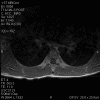

Panel A to E are MR images. Panel F and G are taken from intraoperative cytologic preparation. Panel H to M are taken from frozen section. Panel N and O are from paraffin section. These sections are stained by hematoxylin-eosin stain. Panel P is immunohistochemistry for neurofilament proteins. Panel Q is stained by Luxol fast blue-Periodic acid Schiff (LFB-PAS) stain.

| DIAGNOSIS: Eosinophilic myelitis. |

Pathology of eosinophilic myelitis

Eosinophilic myelitis is featured by lymphocytic infiltration accompanied by a varying intensity of eosinophils. Both the myelin and axons may be damaged. Axonal spheroids can be seen and indicate primary axonal damage rather than secondary damage following demyelination 14, 15. Destruction of axons in the lesion may well explain the relatively poor recovery of this condition. There is increase in eosinophils in CSF in the our under discussion. However, the CSF studies are normal in two previous studies 14, 15.

The eosinophils play an important role in causing the damages. Infiltration by eosinophils and depositions of activated products of eosinophils are commonly seen in atopic disorders, such as atopic bronchial asthma, allergic rhinitis and atopic dermatitis. The presence of atopic diathesis as well as eosinophilic cationic protein deposition suggests that atopy may represent one of the risk factors for developing eosinophilic myelitis. Eosinophilic cationic protein is one of the neurotoxic proteins released by activated eosinophils Eosinophil cationic protein and other products of eosinophils such as major basic protein have been shown to be neurotoxic. The infiltrating eosinophils may therefore well contribute to the neural damage.